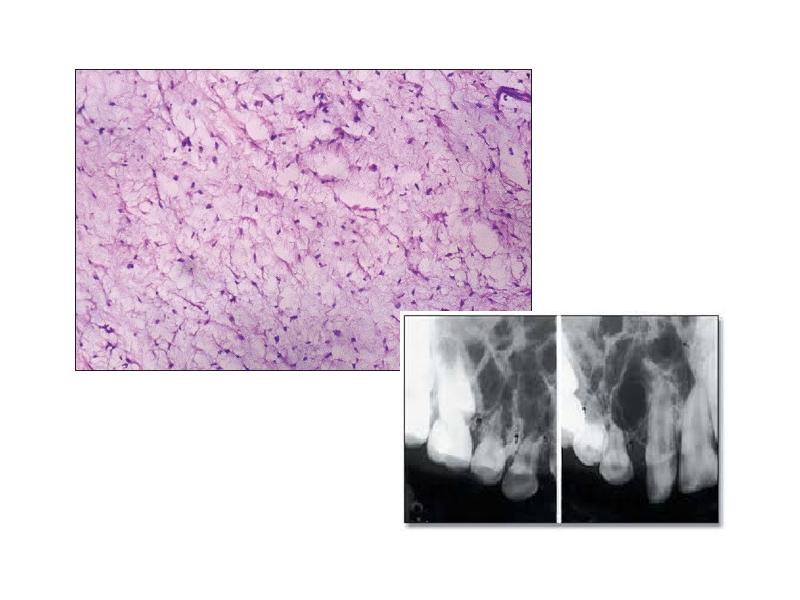

- 35. Одонтогенная миксома Третья по частоте встречаемости среди одонтогенных опухолей (после одонтомы

- 37. Первичный внутрикостный рак Развивается из островков Малассе на фоне амелобластомы из